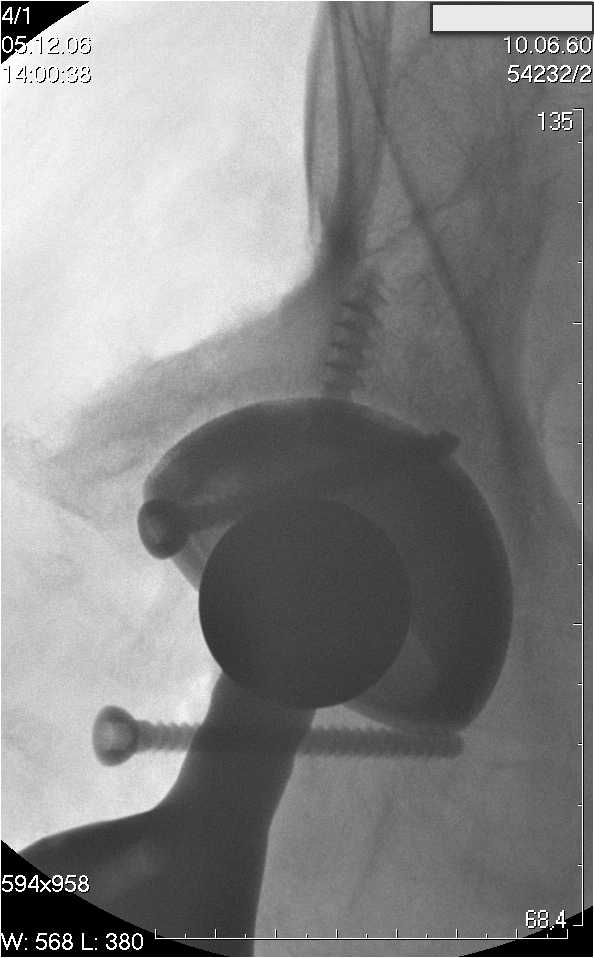

Уважаемые коллеги.В 3 Центральный Военный Клинический Госпиталь имени А. А. Вишневского, что в Красногорске, Московской области, в отделение эндопротезирования крупных суставов поступил пациент 1960 года рождения Жалобы при поступлении: на боли в области левого тазобедренного сустава (больной указывает на точку расположенная в середине условной линии между седалищным бугром и большим вертелом), усиливающиеся в начале ходьбы, при опоре на левую ногу с иррадиацией болей по наружной и наружно-задней поверхности левого бедра, левый коленный сустав; снижение объема движения в левом тазобедренном суставе, снижение опорной способности левой нижней конечности, хромоту на левую ногу, необходимость использования дополнительной опоры (костыли) при ходьбе, снижение объема двигательной активности из за болей в суставе.В анамнезе: Со слов больного, согласно медицинских документов, в 1989 году получил травму левой нижней конечности: закрытый перелом левой вертлужной впадины с центральным вывихом головки левой бедренной кости. Лечился консервативное. В процессе лечения сформировался посттравматический артроз, укорочение левой нижней конечности до 5 см. 25.04.2005 года в Подольском Окружном Госпитале Министерства Обороны выполнено: одномоменто, остеосинтез заднего края вертлужной впадины фрагментом резецированной головки бедренной кости и тотальное эндопротезирование левого тазобедренного сустава бесцементным эндопротезом "VERSIS ET" с бесцементной чашкой TRILOGY. Послеоперационный период осложнился ранним нагноением области эндопротеза, в результате санаций очага инфекции и антибиотикотерапии, активного промывного дренирования антисептиками, послеоперационная рана зажила. После операции, со слов больного, через два месяца в полном объеме стал нагружать левую нижнюю конечность. В течение полгода, после операции чувствовал себя вполне удовлетворительно. С марта 2006года стал отмечать появление болей в области тазобедренного сустава, то в области паха, то в области левой ягодицы. С августа месяца отмечает те жалобы, с которыми он сейчас к нам обратился. Температура тела, после заживления раны, нормальная. В анализах крови, лейкоциты около 7 тыс, формула нормальная, СОЭ 12 мм ч. Локально: при осмотре обеих нижних конечностей, анатомическая ось конечности не нарушена; отмечено относительное укорочение левой н\конечности на 1.5 см., гипотрофия мышц левого бедра 3 см, голени 2 см, симптом. Объем движений в тазобедренных суставах: правый~ сгибание- 60 гр, разгибание-180 гр ,отведение- 35 гр, левый~ сгибание- 110 гр , разгибание-170 гр , отведение-15 гр. Контуры других суставов н/конечностей обычные, объем движений в них не страдает. Пульсация на артериях конечностей удовлетворительная. Неврологические нарушения конечностей отсутствуют, рефлексы на обеих н/конечностях одинаковые, чувствительных нарушений нет. Осевая нагрузка на левую нижнюю конечность вызывает боль в точке расположенная в середине условной линии между седалищным бугром и большим вертелом. Отмечается пигментация и пастозность нижней трети обеих голеней и стоп, характерная для посттромботической болезни. На Цветном дуплексном сканировании сосудов нижних конечностей: Нестенозирующий атеросклероз обеих бедренных и подколенных артерий . Гемодинамически значимых препятствий кровотоку в магистральных артериях ног не выявлено. Глубокие и поверхностные вены нижних конечностей проходимы. Умеренная недостаточность клапанов подколенных вен. Данных за тромбоз глубоких вен на момент осмотра не получено.А вот что пишет наш рентгенолог: На серии рентгенограмм области левого тазобедренного сустава определяется тотальный бесцементный эндопротез. Вокруг тени чашки эндопротеза определяется ободок остеорезорбции. Кроме того, визуализируется деформированный костный винт фиксирующий консолидированный отломок вертлужной впадины, вплотную прилегающий к тени чашки эндопротеза. Заключение: Рентгеновские признаки нестабильности чашки тотального эндопротеза. Лучевая нагрузка: 6 мЗв. У нас в отделении разошлись мнения: начальник мой утверждает, после сравнения снимков, принесенных больным от августа и октября 2006года и наших рентгенснимков, что у больного нет нестабильности вертлужного компонента, и что надо назначит курс консервативной терапии: препараты кальция, миакальцик, увеличить осевую нагрузку на левую нижнюю конечность, ЛФК направления на укрепление мышц бедра, ягодиц, физиолечение. А я утверждаю, что у больного клиника нестабильности вертлужного компонента, и необходима ревизия вертлужного компонента, не исключено даже наличие инфекции под чашкой эндопротеза (не смотря на отсутствие клинических признаков инфекции). В результате проводимой консервативной терапии, боли у больного усилились. Помогите рассудить нас, мы готовы выслушать ваши мнения по этому поводу. С уважением Батал Шушания.3 ЦВКГ имени А. А. Вишневского

Ув. Коллега.Четких рентгенологических признаков нестабильности вертлужного компонента действительно нет. Здесь, кроме нестабильности, можно искать причину в поясничный отдел позвоночника(Hip-spain синдром - всё-таки 15 лет ходил с укорочением),либо сделать спиральный КТ и посмотреть, нет ли несращения в области старого перлома вертлужной впадины. Зачастую ложные суставы подвздошной, седалищной, а иногда и лонной костей являются причинами несостоятельности эндопротезов.

поясничного отдела позвоночника. Есть зона остеолиза вокруг чашки, но как правило, дополнительный винт держит чашку достаточно хорошо, и даже при наличии микроподвижности, это не сопровождается столь ярким болевым синдромом. Поэтому, я бы сделал следующее: МРТ позвоночника, пункцию ТБС для исключения инфекционного процесса. Ревизию рассматривал бы как крайний вариант, учитывая выполненную костную пластику и отсутствие явных признаков нестабильности.

уважаемый коллега, Антон Вакуленко. Спасибо за четкий, расписанный по пунктам план действий. При поступлении пациента в отделение, я думал точно как вы. Но на следующий день, выполнил многопроеционное рентгенисследование, показал невропатологу, и доложил начальнику отделения о больном.После разбора пришли к следующему, да у больного действительно нестабильность вертлужного компонента, есть зона лизиса в месте костного аутотрансплантата, а в месте фиксаци чашки деротационным винтом четко выраженный контакт чашки с костной тканю. Мы пришли к выводу,что лизис костного аутотрансплантата из за осевой перегрузки на фоне незавершенного ремоделирования (вес больного 130 кг). Потому мы и приняли план вышеуказанного лечения. Провели беседу с больным, больной согласился с нами. Через 3-6 месяцев мы оценим эффективность лечения и доложу. Возможно и придется тогда идти на ревизию с заменой только вертлужного компонента а может и придется удалить весь эндопротез с установкой спейсера.. посмотрим.....